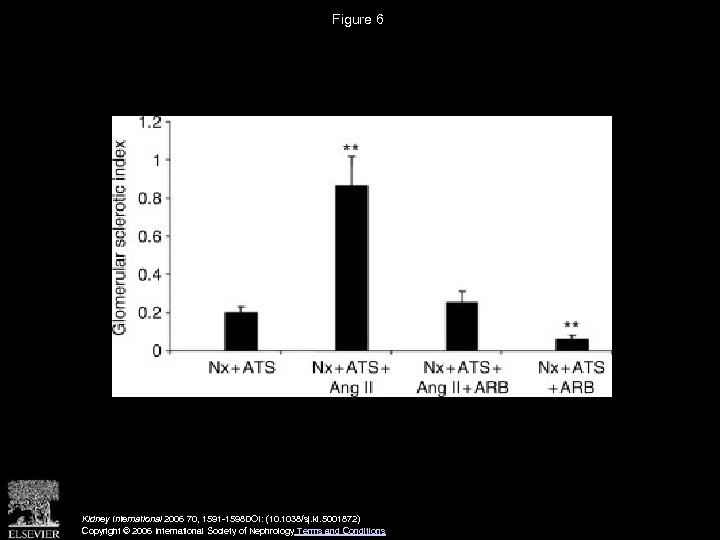

Figure 6 Kidney International 2006 70, 1591 -1598 DOI: (10. 1038/sj. ki. 5001872) Copyright © 2006 International Society of Nephrology Terms and Conditions